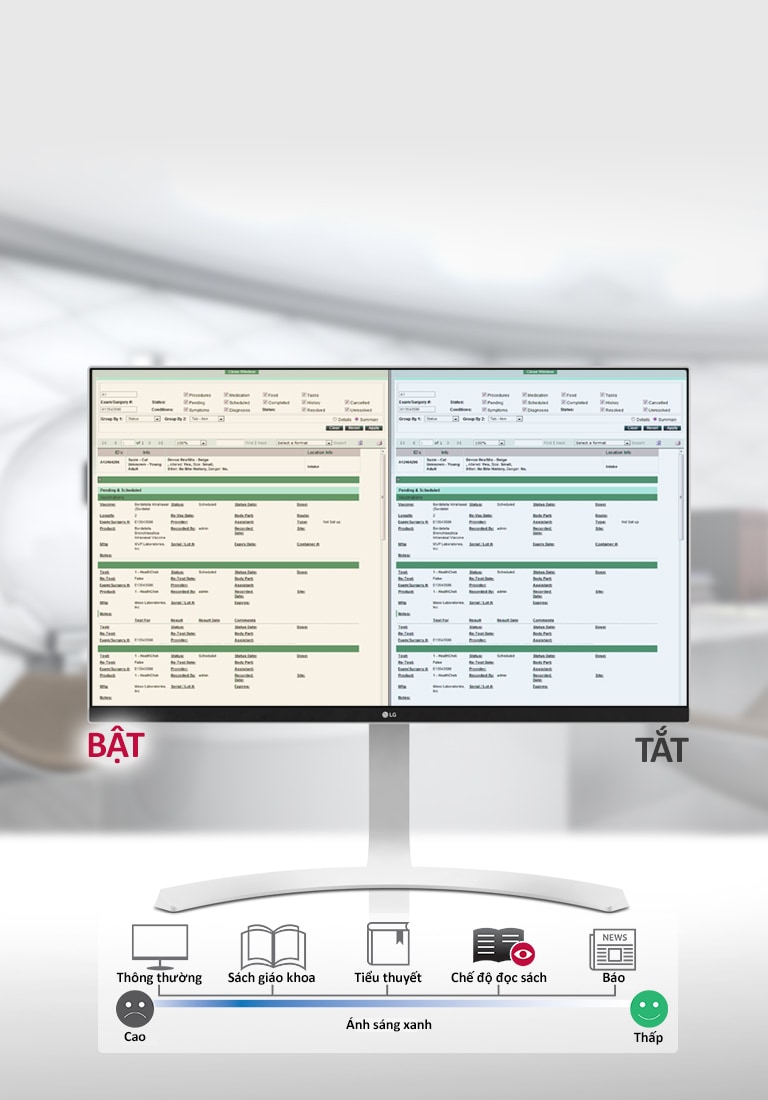

Chế độ đọc sách

CÓ